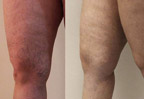

Xilas edilmiş aşağı ətraflar

Əvvəl və Sonra